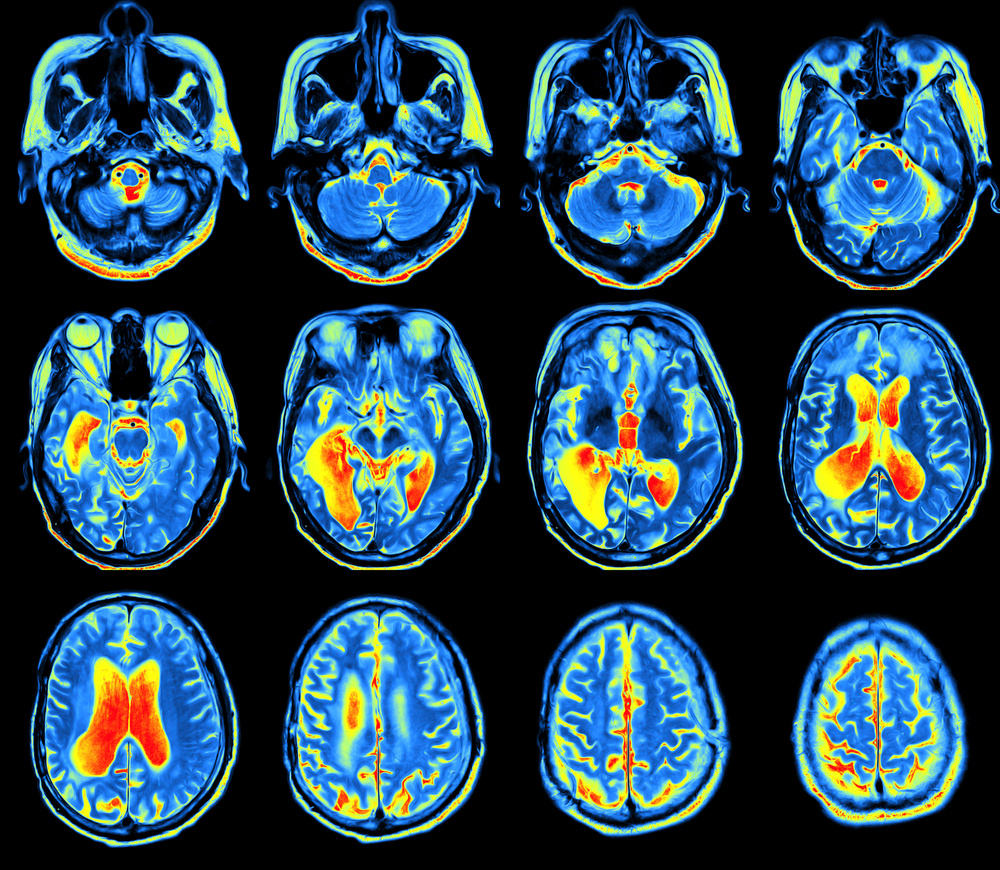

• Функциональная МРТ (fMRI): регистрирует изменения кровотока, связанные с активностью нейронов.